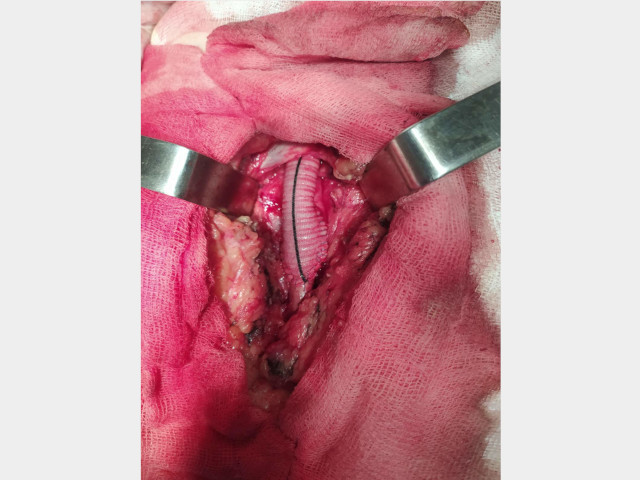

Пациент 1.

Диагноз: Мультифокальный атеросклероз. Стеноз внутренней сонной артерии 20% справа и 25% слева. ХНМК 1. Стеноз общей подвздошной артерии 75% справа и 65% слева. Окклюзия бедренно-подколенных сегментов с обеих сторон. ХИНК II Б степени справа и ІІ А степени слева.

26.02.2020 производилось плановое оперативное лечение пациенту с многососудистым атеросклеротическим поражением.

Больному было сделано аорто–бифеморальное шунтирование и протезно–подколенное шунтирование справа. (Операционная бригада: Лящук А.В., Нижельский В.Е., Редин Д.Е.; Анестезиолог: Никитич А.В.)

После операции у больного пульс на оперированной стопе нижней конечности.